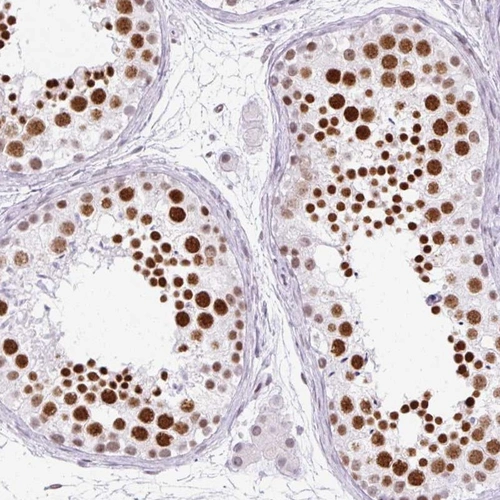

Immunohistochemical staining of human testis shows strong nuclear positivity in cells in seminiferus ducts.